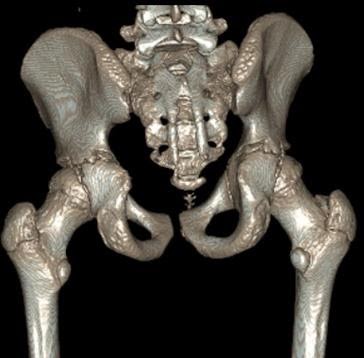

MRI demonstrated an anterior labral tear, but also lateral acetabular ‘under coverage’. The subsequent CT with 3D reconstruction images (Figs 17 & 18) – the gold standard investigation – shows dysplasia principally of the posterior wall.

Figure 17 CT (anterior view)

Figure 18 – CT (posterior view)